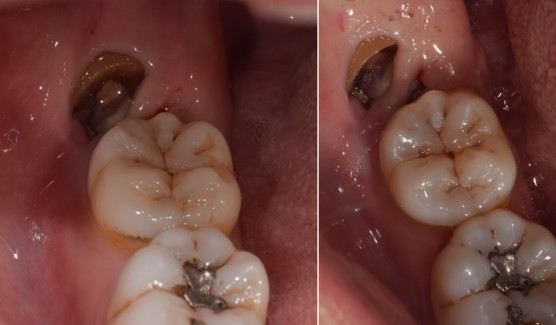

사랑니#48 사랑니 발치

치료 기간  2024. 03. 12 당일 치료

cc. #48 발치 원하심

K01.173 하악 제3대구치 의 매복

신경손상, 악관절의 외상, 드라이소켓(건선치조골염) 등이 있을 수 있습니다.

※ 상기 사진은 본원 권대근 대표원장이 치료한 환자분의 동의를 받은 이미지 사진으로 실제와 차이가 있을 수 있습니다.